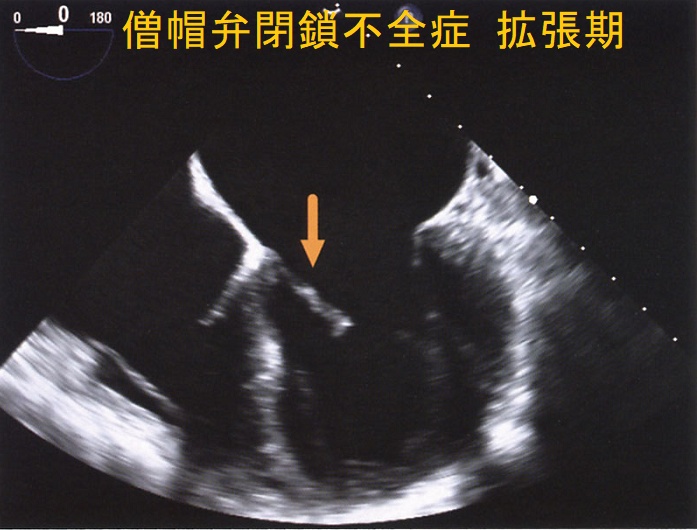

僧帽弁閉鎖不全症(MR)は、

- 僧帽弁逸脱:閉塞性肥大型心筋症、甲状腺機能亢進症の30%に起こる

自己免疫性に粘液多糖類が蓄積し、僧帽弁の粘液水腫性変化が生じます

- 甲状腺機能亢進症/バセドウ病の33%

- 甲状腺機能低下症/橋本病の36%

特に循環血液量・心拍出量が増加する甲状腺機能亢進症/バセドウ病では、僧帽弁腱索/乳頭筋断裂を引きおこす危険性が高い。(J Endocr Soc. 2018 Sep 17;2(11):1246-1250.)[Endocrinol Diabetes Metab Case Rep. 2022 Jul 1;2022:22-0298.]

僧帽弁腱索/乳頭筋断裂がなく、粘液腫性変性による中等度から重度の僧帽弁閉鎖不全症(MR)なら、甲状腺機能の正常化に伴い改善する可能性があります。[BMJ Case Rep. 2021 Feb 4;14(2):e239626.]